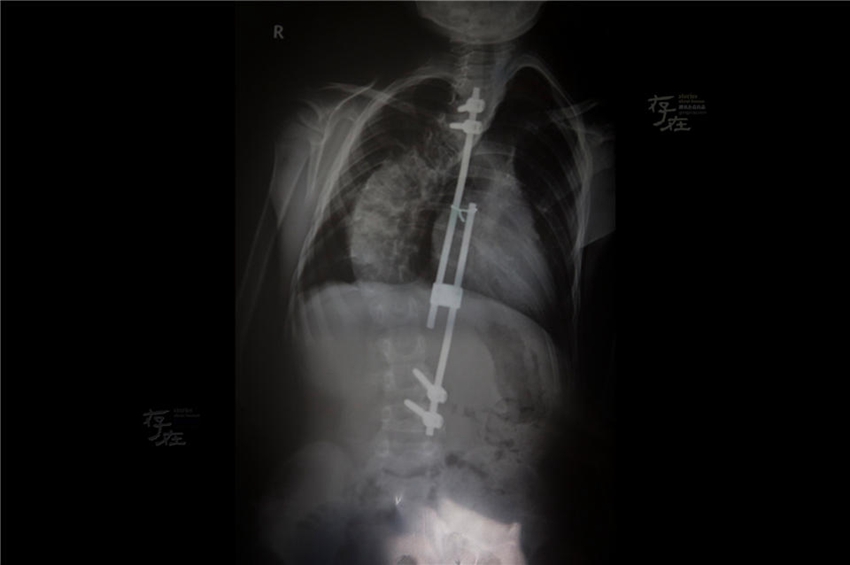

1? 26?, 8? ?? ??????(才仁東周)? X-?? ??? ??? ?? ??.

[??? ???? 4? 21?] 1? 27?, ??? ??(玉樹)?? ??? ????? ?? 11?? ???? ????. ???????? ????? ?? ?? ??? ?????(朝陽醫(yī)院)? ??? ??? ?? ?? ? ??? ???. (??: ??? ??: ???)